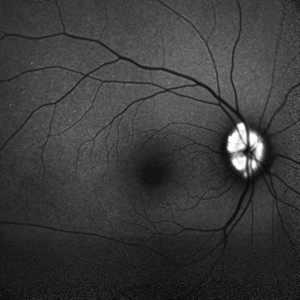

Optic nerve head drusen

Dec 26 2022 by Vaidehi Sathaye

FAF photograph of RE of a 32 year old female with Optic nerve head drusen

Photographer: Dr. Vaidehi Sathaye

Imaging device: Mirante

Condition/keywords: drusen of optic disc